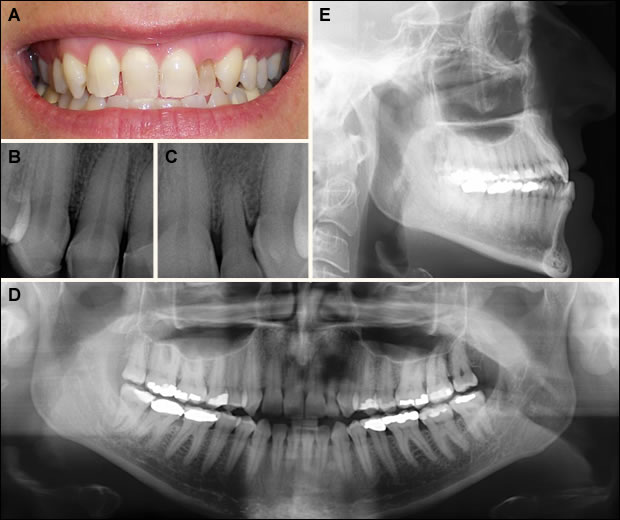

Fig 1: Pre-operative view.

A. Several incisors exhibited anterior crossbite.

B. Tooth # 7 was congenitally missing and tooth #8 erupted in site #7.

C. Tooth #10 was congenitally missing. A retained deciduous tooth was present in site #10.

D. A supernumerary incisor erupted in site #8. Tooth #6 and 11 were rotated.

E. The skeletal relationship was a Class III.